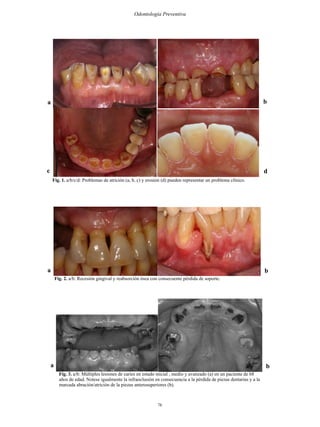

En estos pacientes es igualmente común observar mayor exposición de cemento y dentina

(2). Por lo que problemas de abrasión, afracción, atrición y/o erosión (Figura 1) pueden

estar en estado avanzado y representar un problema clínico.

Con el envejecimiento se producen variaciones en la estructura de los tejidos periodontales

que se expresan en la retracción gingival, denudando el cemento radicular (Figura 2). En

el hueso alveolar, es común observar un menor trabeculado, éste se presenta osteoporótico,

más frecuentemente en mujeres postmenopáusicas. El ligamento periodontal se presenta

atrófico, en especial cuando el diente está en desoclusión. Estos cambios contribuyen a la

susceptibilidad periodontal del paciente de edad avanzada (16).

Fig. 1. a/b/c/d: Problemas de atrición (a, b, c) y erosión (d) pueden representar un problema clínico.

Fig. 2. a/b: Recesión gingival y reabsorción ósea con consecuente pérdida de soporte.

Fig. 3. a/b: Múltiples lesiones de caries en estado inicial , medio y avanzado (a) en un paciente de 68

años de edad. Notese igualmente la infraoclusión en consecuencia a la pérdida de piezas dentarias y a la

marcada abración/atrición de la piezas anterosuperiores (b).